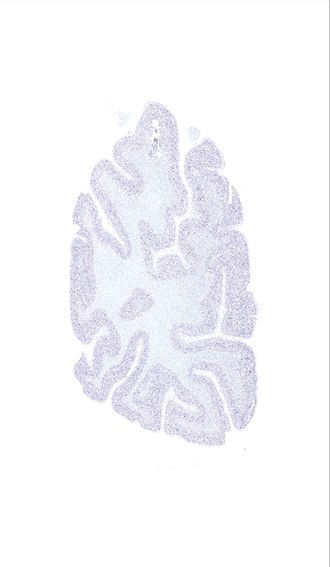

Hi-Resolution Sections · Cells (Nissl Staining) · Virtual Microscopy

Frontal sections (Nissl) from the Atlas Brain:

Slice ID:

r5-0450

Plate NR:

66-67

Position:

88,8 mm